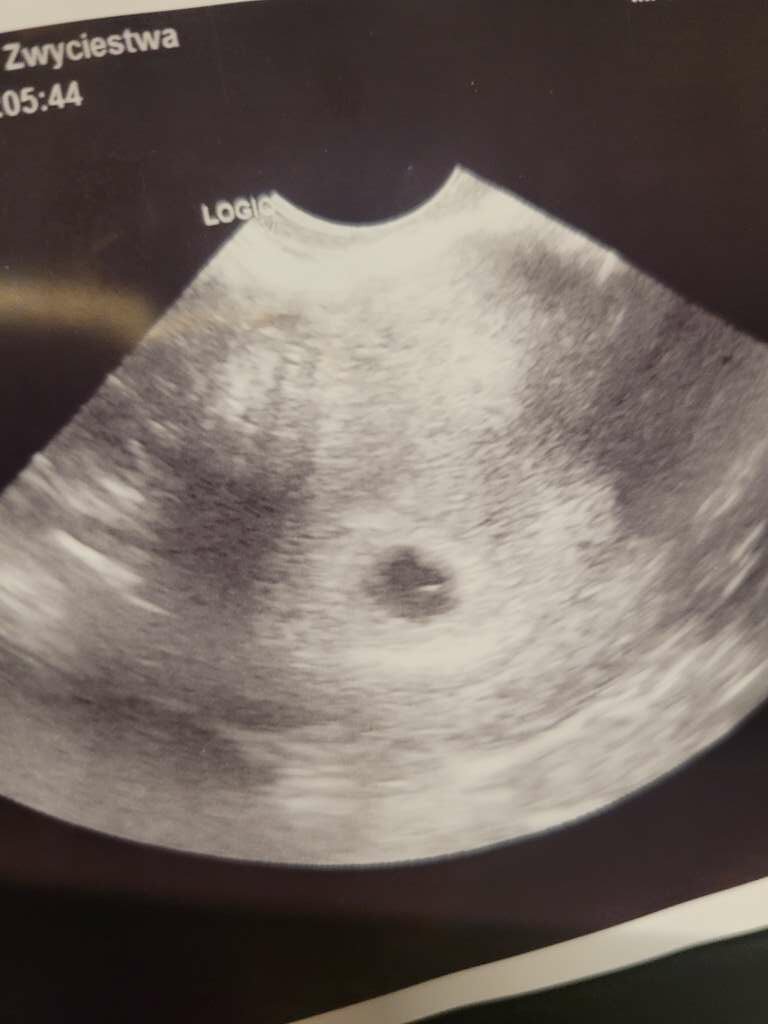

Natomiast wczoraj zestresował mnie lekarz z luxmedu... to było 5+4 i zobaczyl pęcherzyk... zapytam tylko czy widzi to co.powinien na tym etapie na co.on, że nie... bo to 6 tydzien i.powinien być już zarodek.

Wyszłam z przekonaniem, że pewnie skończy się jak.poprzednio... z tego stresu nie zapytalam .nawet czy jest pęcherzyk zóltkowy, chciałam tylko wyjsc i chciało mi sie ryczeć mimo, że ja z tym "twardych"... (mam zdjecie ale nie znam się) jestem zdołowana i chyba szukam wsparcia... by ktoś powiedział, że na tym etapie ciąży również nie ma jeszcze zarodka...